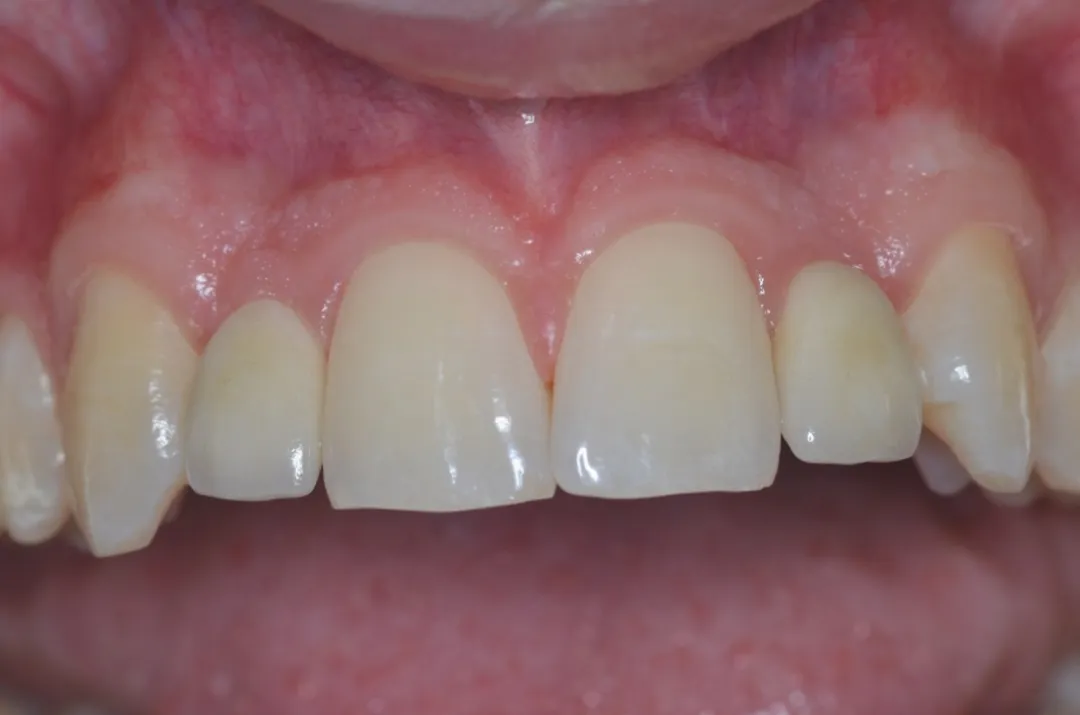

图 48 :术后 1 年口内情况。

图 49 :术后 1 年随访 X 线影像。